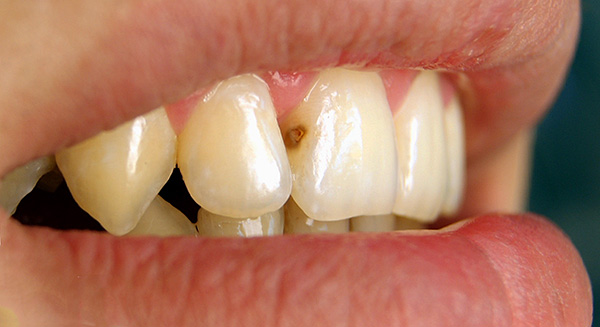

A fotografia abaixo mostra uma fístula na gengiva acima do dente da frente “morto”: